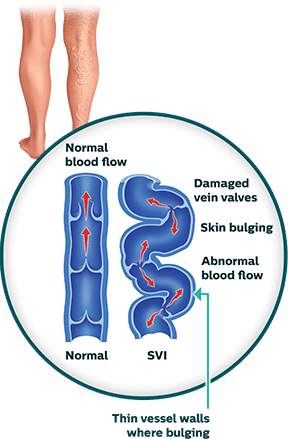

Superficial Venous Insufficiency (SVI)

Superficial venous insufficiency (SVI) is a common condition that occurs when there is decreased blood flow from the leg veins up to the heart.1 Without adequate flow, the blood can pool in the leg veins and result in common conditions, such as spider veins, reticular veins and varicose veins. Approximately 25 million people in the United States suffer from varicose veins—enlarged blue, red, or flesh-colored veins that are raised above the surface of the skin.2 Like varicose veins, spider veins are also swollen veins that appear through the skin, but are closer to its surface and resemble tree branches with short, jagged lines. Although spider veins are not usually symptomatic, the accompanying reticular veins, found deeper in the skin, often cause discomfort. Reticular veins are also referred to as “feeder” veins. These vessels are smaller branches which can originate from bigger varicose veins. All three types of venous problems appear on the thighs, backs of the calves, or ankles. Although not life-threatening, SVI can cause problematic skin changes and can progress over time.

Superficial veins have less muscle support than deep veins, so any condition that puts pressure on the legs or surrounding areas can lead to pooling of blood in the extremities. Common pressure inducers are obesity, pregnancy, and standing for long periods, as well as sitting and limited movement. The likelihood of acquiring SVI increases if other family members have it and with age. Over time superficial veins weaken and aren’t able to push blood back up the heart.3 While some people have minor symptoms that are simply cosmetic, others have more debilitating ones. Common symptoms of SVI are a feeling of heaviness in the legs, aching, swelling, throbbing and itchy skin. Over time this can lead to inflammation of the varicose veins, scaling of the skin and eczema, thickening of the skin and can ultimately result in leg ulcers. SVI symptoms include:4